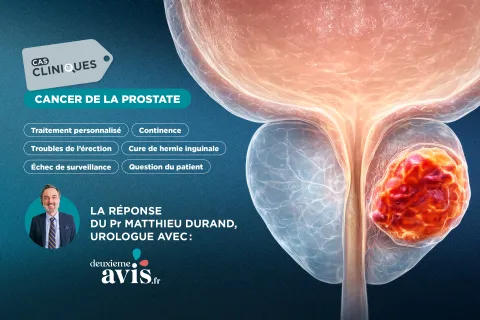

Cas clinique en urologie du Pr Matthieu Durand : quelle stratégie locale pour ce cancer de la prostate après 9 ans de surveillance active ?

Après 9 ans de surveillance active, un patient de 66 ans initialement porteur d’un cancer de la prostate à faible risque présente aujourd’hui une progression biologique marquée, associée à une lésion antérieure PIRADS 4 à l’IRM et confirmée comme localisé...